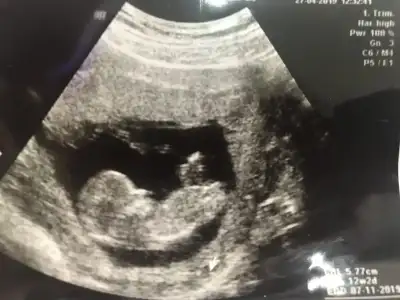

Cinsiyet tahminlerini alalim lutfen. Şu cikintiyi pipiye benzettim 😄 moonyaz moonyaz burda görünüyor bak

Cinsiyetle alakali asla ama asla yorum yapmadı. Israrla sorduk bi dahaki ay soylerim deyip durdu. Ama bence erkek, cunku nuba gore pipiye benzer bi seyler gordum size foto aticam 😄

Bizde bugün gittik doktora, ikili test yapmadı desteklemiyormuş doktor. radyoloji uxmanı doktora yönlendirdi. ense kalınlığına ve detaylı ultrasonla iç organlarına baktılar. normal çıktı her şey 😇 ben oyumu erkekten yana kullanıyorjm dedi bebişe. sizce cinsiyeti nedir? nubdan anlayanlar?? ☺️☺️